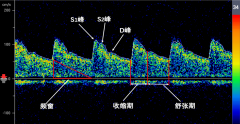

經(jīng)顱多普勒檢查參數(shù)介紹

由于TCD具有很強(qiáng)的操作依賴(lài)性,血管的識(shí)別通常是在間接參數(shù)的基礎(chǔ)上進(jìn)行,因此熟練掌握TCD的操作技巧非常重要。